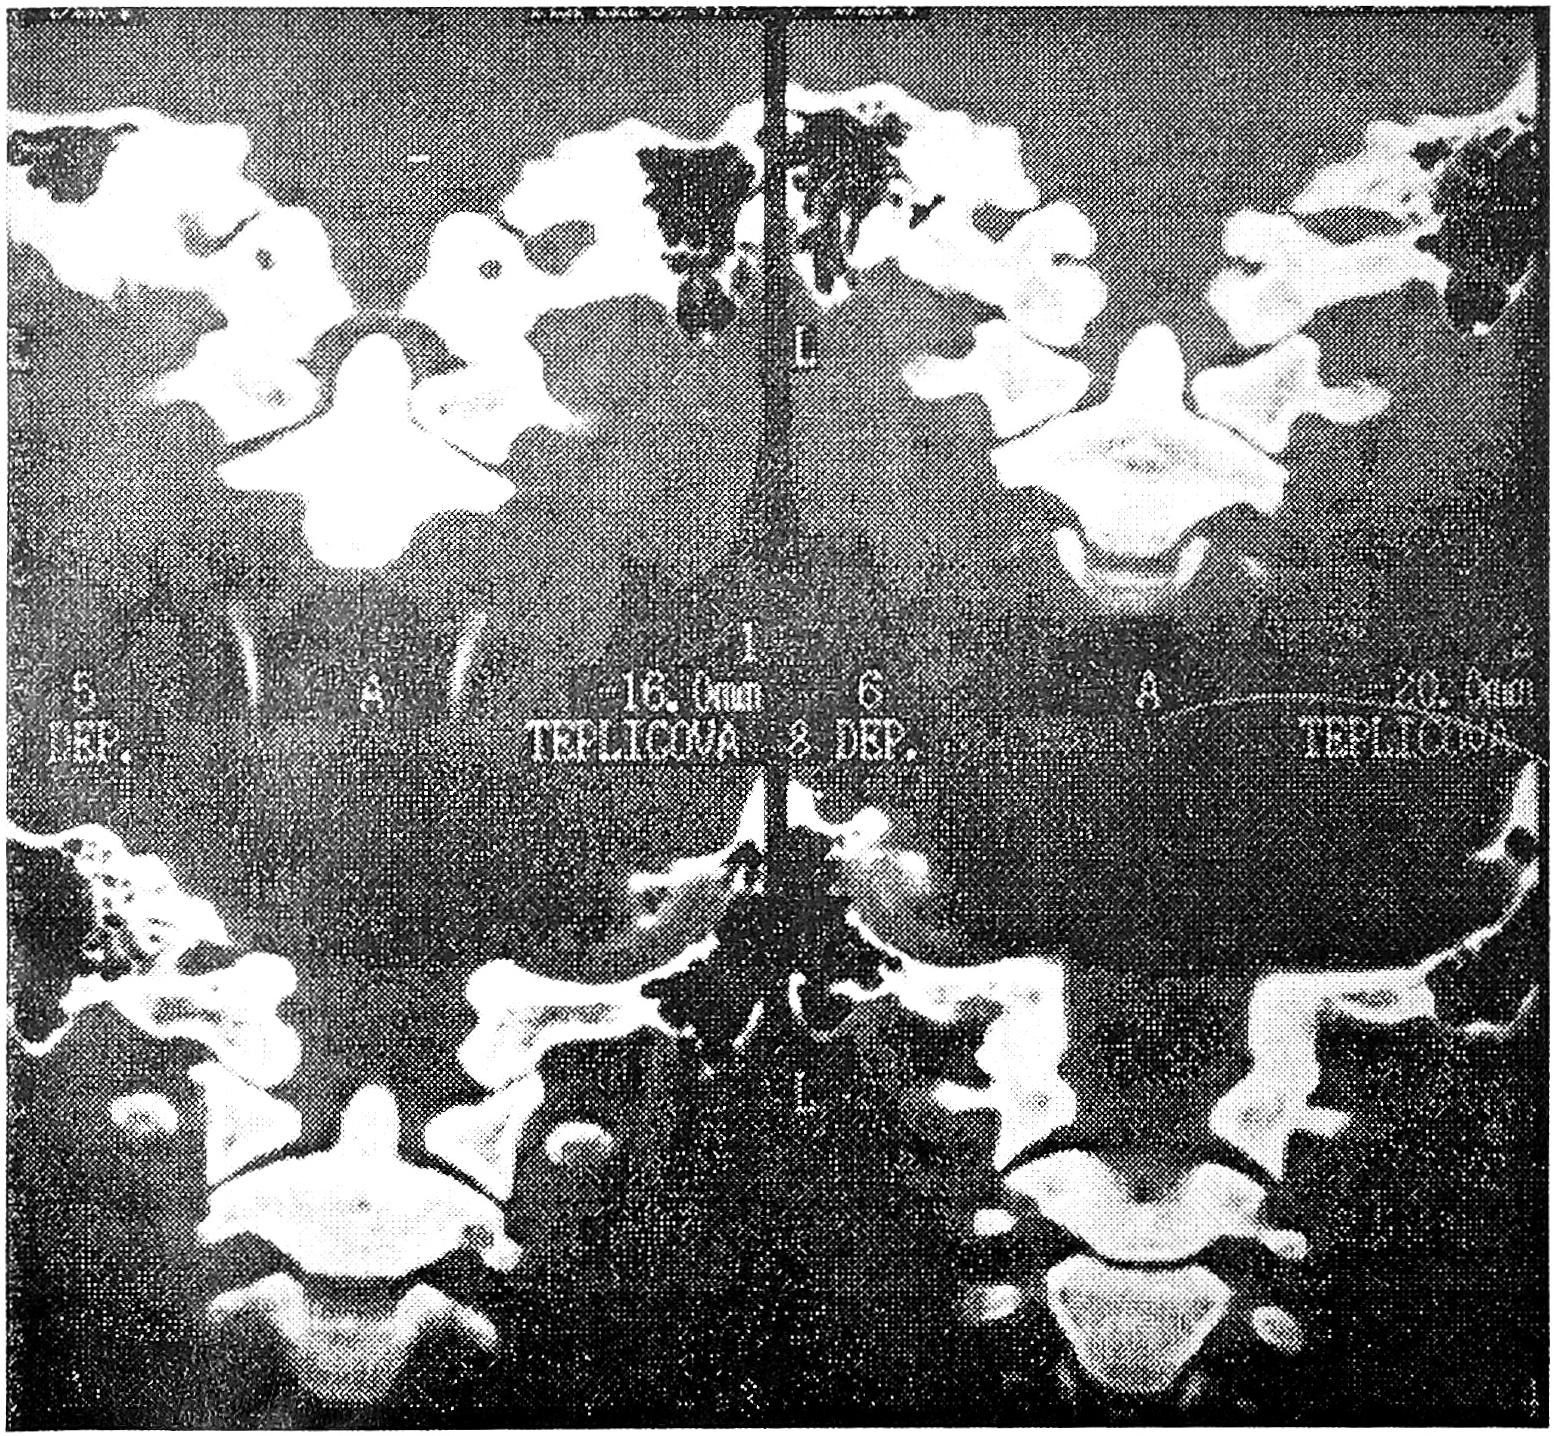

При застарелых ротационных подвывихах атланта этот метод позволяет ясно видеть характер дислокации, что важно при ее устранении (см. рис. 1 на вклейке).

Рис. 1. Зонограмма верхнешейного отдела позвоночника больного с застарелым ротационным подвывихом атланта: определяются асимметричное положение зубовидного отростка, несовпадение суставных поверхностей боковых атлантоаксиальных суставов.